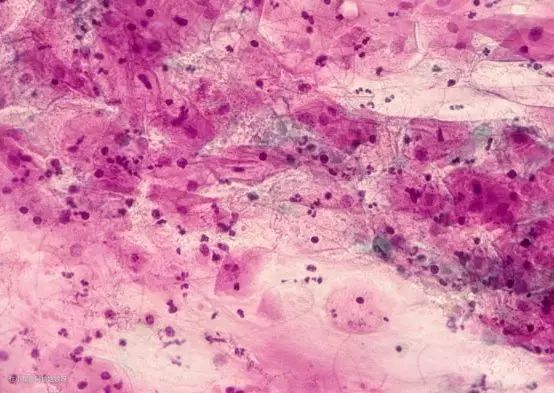

如果长期不进行处理,特别容易引发霉菌性阴道炎和盆腔炎,可以看下中科院在显微镜下研究的内裤附着霉菌,这就是导致霉菌性阴道炎的主要诱发因素,为了个人健康着想,所以我现在挑选内衣物洗衣机时,会更倾向洗烘一体!

显微镜下内裤上的细菌,对炎症有直接影响...